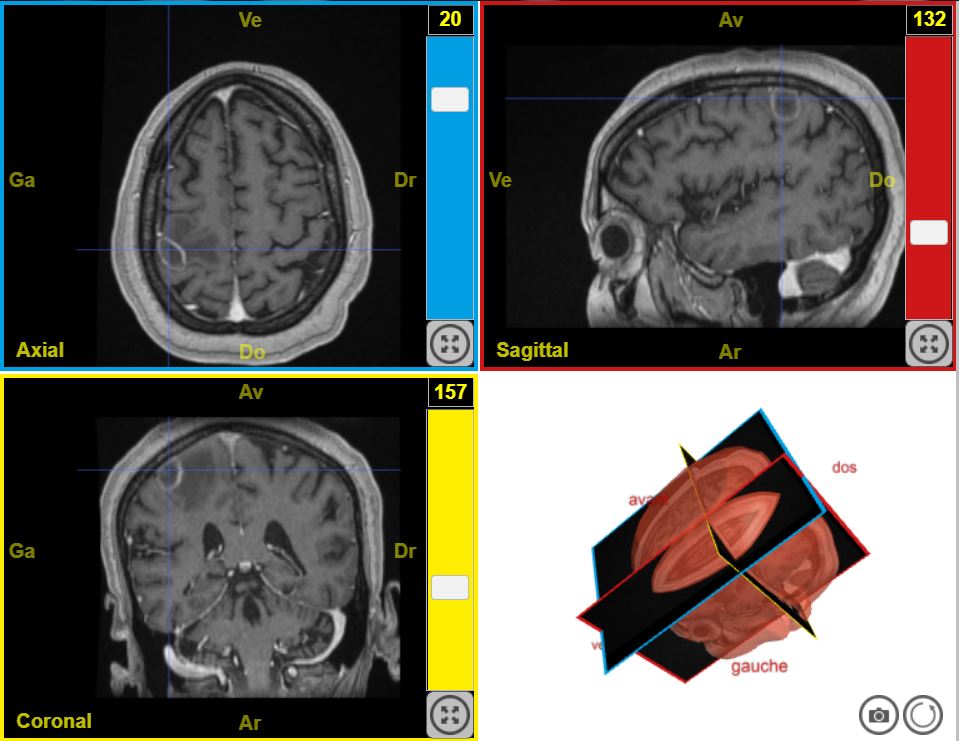

CaptureDeficit moteur T1